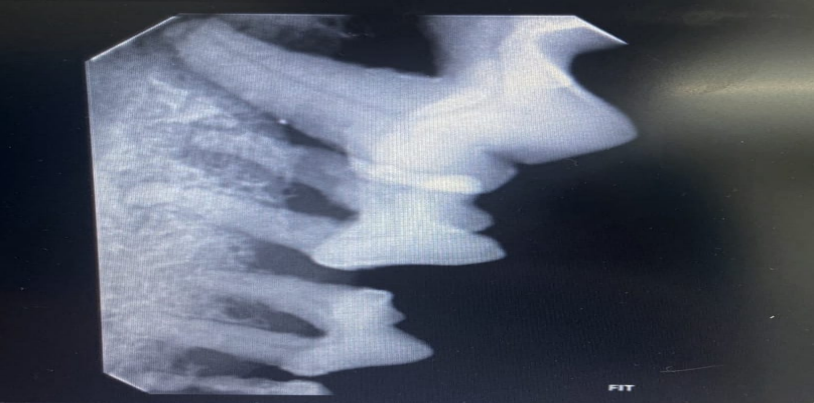

Figura 1 – Radiografia intraoral evidenciando perda óssea alveolar.

Figura 5 – Radiografia intraoral evidenciando destruição óssea alveolar e comunicação oronasal.

Esses achados corroboram as descrições de Harvey & Emily (2016), que relatam a periodontite avançada como a principal causa de comunicação oronasal e fístulas infraorbitárias em cães idosos. O envolvimento do quarto pré-molar superior (P4), cuja raiz distal está próxima ao seio maxilar, foi compatível com a literatura, que identifica esse dente como o mais frequentemente afetado (Wiggs & Lobprise, 2013; Jensen et al., 2017).